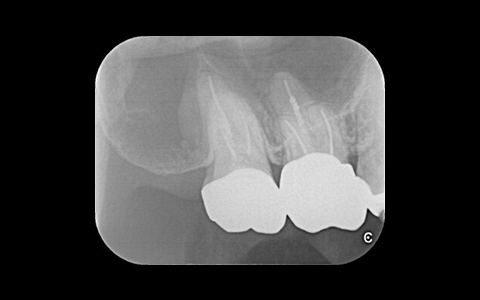

治療前

治療後

黄色い矢印の歯が治療前の対象歯です。レントゲンで観察すると、歯の根のお薬が充分には入っていないようです。

麻酔をして歯の中をマイクロスコープで観察すると、元々あった3つの根だけでなく「もう一つの4番目の根」があったのです。根管治療自体は容易に行えましたが、歯の中を明るく拡大できるマイクロスコープを持っていない歯医者さんでは見つけるのが困難だと思われます。この4つ目の歯の根を治療することにより痛みは消失し「抜歯してインプラント」になるという悪循環に陥らず済みました。根管治療はマイクロスコープを使って精密に、また丁寧に行えば歯を長く保たせることができる治療です。やはり神経自体を残すという選択が、歯の保存にとって一番良いということは間違いありません。

| 費用 | デンタルドック:55,000円 根管治療(奥歯):176,000円 MTAセメント:33,000円 歯の土台:33,000円 合計:297,000円 |

| リスク・副作用 | 治療中に一時的な咬合痛や冷温水痛、若干の歯肉の腫れ、発赤などを生じることがあります。また仮歯の時期には仮歯の脱離や破損の可能性、舌感などに違和感を覚えることがありますが、本歯に移行するまでに通常消失します。 ※すべて症例による違いや個人差があります。 |

※表示金額は全て税込みです。